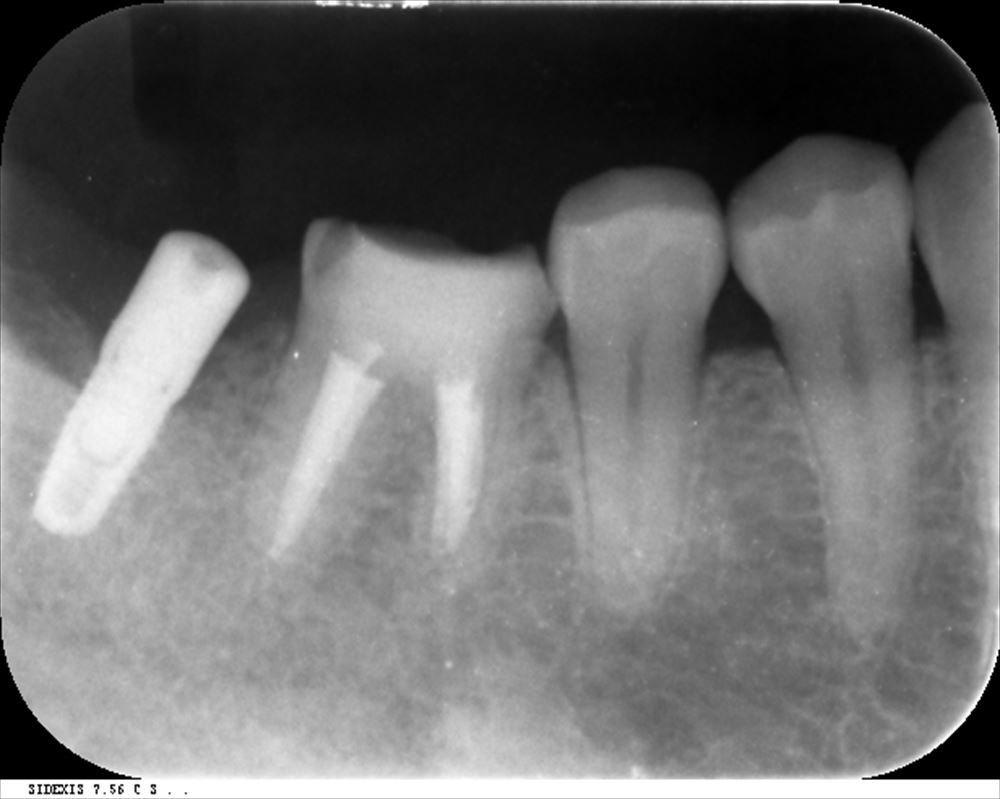

他院でリーマー破折。器具が残っています。

CTでも確認 ML根

取れました!!今日根管充填。症状もないです。

後ろのインプラントは私が去年埋入。同時に上部を作っていけそうです。歯の保存をまず考えています。